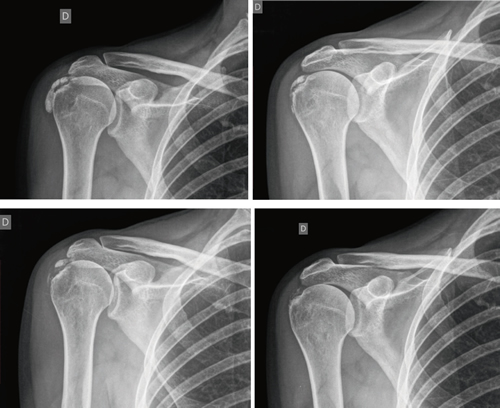

Figure 3

Figure 4

Figure 5

Figure 6